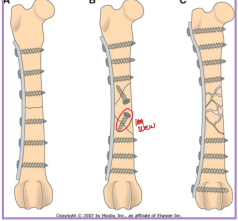

Types of External Skeletal Fixation

What:

Pins: Engage bone, provide stabilization

Clamps: Secure pins to connecting bar.

Connecting bar: Links clamps and pins.

Types:

Linear: Frame strength ↑ with complexity

Type IA: Unilateral, uniplanar

Type IB: Unilateral, biplanar

Type II: Bilateral, uniplanar

Type III: Bilateral, biplanar

Linear Type 1/A ESF

½ pins

Unilateral, uniplanar

all pins enter one 1 side

all pins going in the same plane (medial→lateral)

Linear type 1B ESF

Unilateral, biplanar

different planes

Linear type 2 ESF

Full pins

Bilateral, uniplanar

same plane (medial → lateral)

Linear type 3 ESF

full pins and ½ pins

bilateral, biplanar

type 1+2

Frame strength increases as frame complexity increases